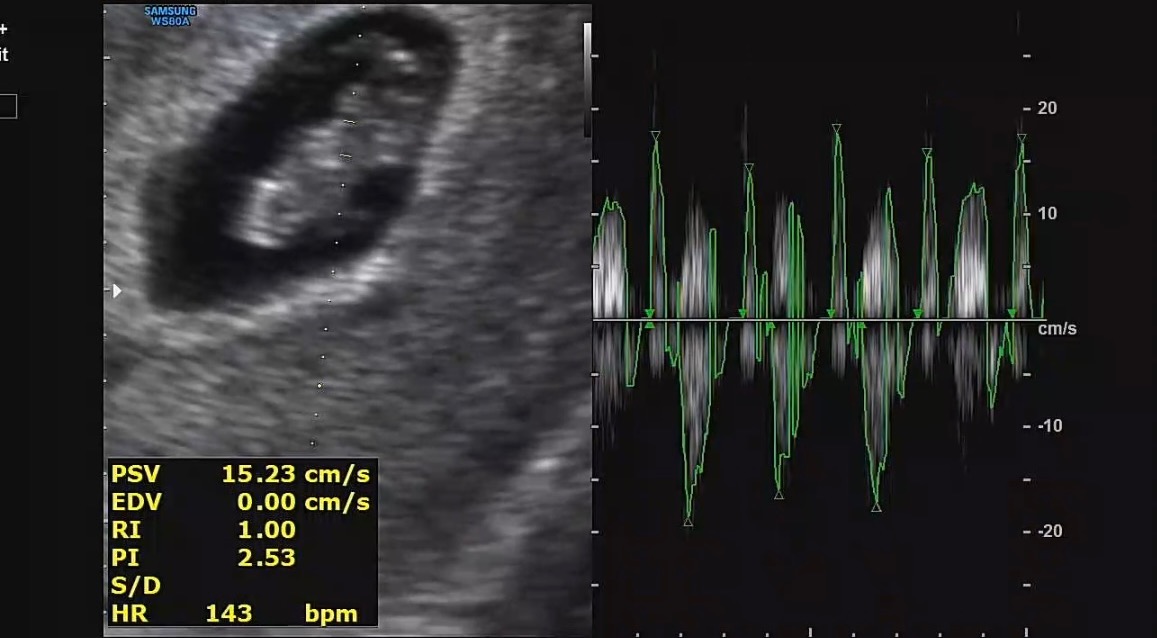

7주 1일차에 병원에 갔는데, 그사이 아기집에서 우리 꿈이가 조금 자라 있었다.

심장소리도 쿵쿵쿵쿵 잘도 뛰었다.^^

처음 듣는 아가의 심장소리에 눈물이 핑 돌았다.오빠도 기분이 이상했다고 했다.